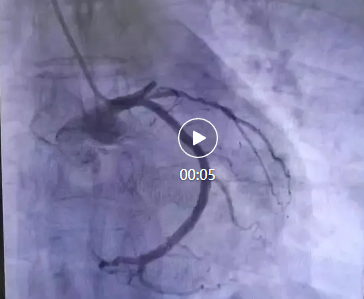

醫(yī)院立即啟動了胸痛中心綠色通道。心血管內(nèi)科李桂武主任、劉興剛主任迅速到位,患者瀕臨崩潰的問道:“大夫,我能活么,孩子媽媽雙目失明,還有倆孩子20歲不到,我要死了,這個家就完了”,李主任、劉主任握著患者的手堅定地說道:“我們的目的不僅僅是讓您活著,還要讓您更有質(zhì)量的生活,所以你要堅持,相信我們。”隨即,李主任、劉主任為張先生進行了冠狀動脈造影,結(jié)果顯示,張先生的前降支近段完全閉塞,這是導(dǎo)致他胸痛的直接原因。李主任當(dāng)機立斷,決定進行急診冠脈支架植入術(shù)。

手術(shù)過程非常順利。醫(yī)生通過導(dǎo)管將支架送至閉塞部位,成功開通了阻塞的血管,恢復(fù)了心肌的血液供應(yīng)。術(shù)后,張先生的胸痛明顯減輕,呼吸也逐漸平穩(wěn)。被轉(zhuǎn)入心臟重癥監(jiān)護室(CCU)進行密切觀察。醫(yī)生為他制定了詳細的治療方案,包括抗血小板藥物、他汀類藥物、β受體阻滯劑等,以預(yù)防血栓再形成、穩(wěn)定斑塊并降低心臟負荷。!